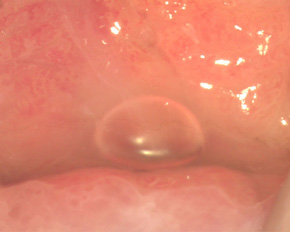

Місце стику двох видів епітелію шийки матки в нормі у жінок репродуктивного віку знаходиться в області зовнішнього зіву (рис). Однак до 22-23 років циліндричний епітелій з цервікального каналу може заходити на 1/3 поверхні шийки матки. Цей стан називається ектопією шийки матки або помилкової ерозією шийки матки. При нормальних результатат мазків і цитології (відсутність запалення, відсутність дисплазії) така ерозія шийки матки не потребує лікування, а лише динамічного спостереження.

Ерозія шийки матки

Описана ерозія шийки матки - вроджена ерозія. Так само існують придбані ерозії шийки матки. Механізм виникнення придбаної ерозії полягає в тому, що відбувається переміщення слизової оболонки цервікального каналу (одношарового, погано виконуючого механічні захисні властивості епітелію) на поверхню (вагінальну частину) шийки матки.

Лікування ерозії шийки матки: пацієнт А

Лікування ерозії шийки матки: пацієнт М

Лікування ерозії шийки матки: пацієнт П